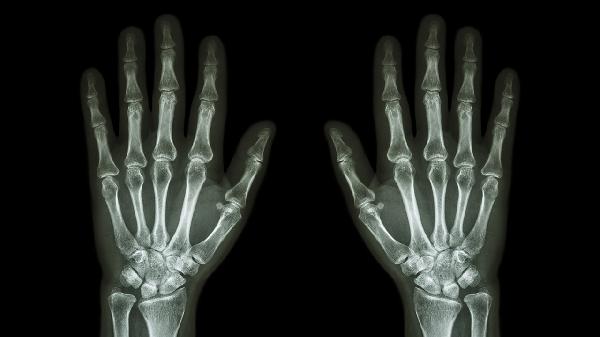

中老年人群因关节退变出现软骨磨损,晨起关节僵硬感明显,X线片可见骨赘形成。疼痛在阴雨天加重,可配合超声波理疗。临床常用硫酸氨基葡萄糖胶囊联合洛索洛芬钠片治疗,严重者需关节腔注射玻璃酸钠。